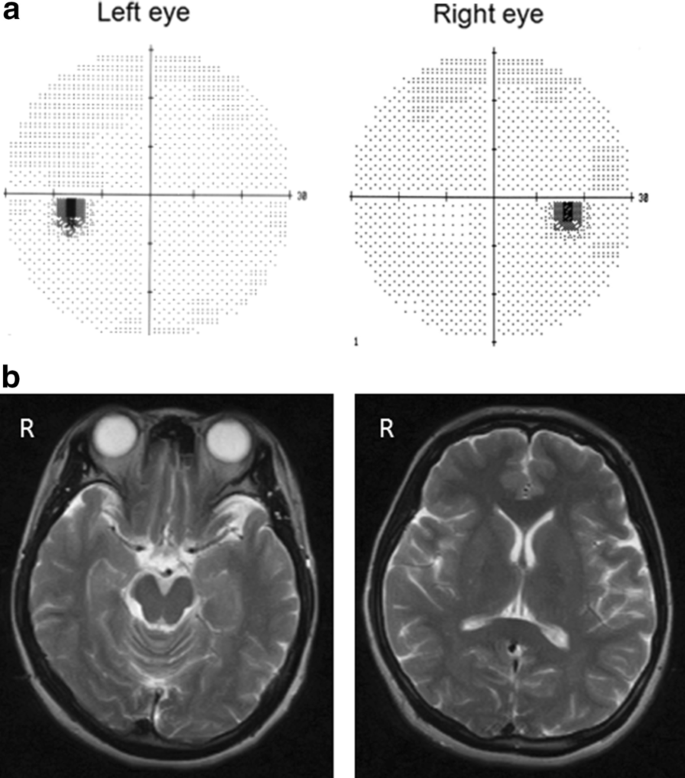

Corrected visual acuities for the right and left eye were 20/20 and 20/25, respectively. Intraocular pressure in both eyes was 15 mmHg. The anterior segments and lenses appeared normal. Multiple yellowish dots in the deep retina were noted around the optic nerve head in both eyes (indicated by the arrows in Fig. 1), and resembled Elschnig’s spots and ischemic choroidal infarcts [9]. Optical coherence tomography (OCT) demonstrated exudative retinal detachments around the optic nerve head in both eyes (Fig. 2). Visual field testing conducted by standard automated perimetry showed left homonymous hemianopsia (Fig. 3a).

We referred the patient to a neurologist for neurological examinations regarding the headache and left homonymous hemianopsia. Results from serum biochemistry tests and a cerebrospinal fluid examination were normal. Magnetic resonance imaging (MRI) revealed edema in the basal ganglions and right occipital lobe (Fig. 3b).

At day 2 after starting treatments with an infusion of a free-radical scavenger (edaravone, 60 mg per day) and anticoagulant (heparin sodium, 10,000 U per day), the left homonymous hemianopsia disappeared (Fig. 4a) and MRI showed subsidence of the brain edema (Fig. 4b). The treatment was continued for 3 days, and the patient's symptoms improved. After improvement of the visual symptoms, cerebral angiography appeared normal (Fig. 5), and the yellowish dots in the deep retina (Fig. 6a) and exudative detachments around the optic nerve heads were no longer observed (Fig. 6b). There has been no recurrence of symptoms during the 4 years of follow-up.

Visual field and magnetic resonance imaging after treatment. a Left homonymous hemianopsia improved at 2 days after infusion of a free-radical scavenger and anticoagulant. b MRI at 1 month after treatment. The lesions in the basal ganglions and occipital lobe were no longer visible in the follow-up MRI